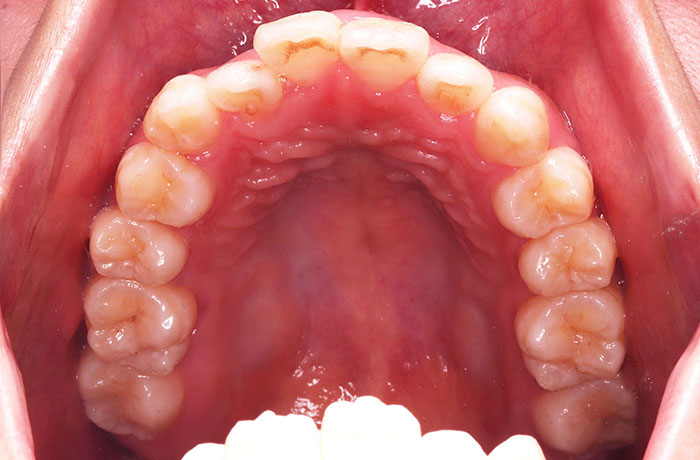

治療前

before

患者の症状 叢生、正中のずれ、上顎左右側切歯の口蓋側転位(交叉咬合)

治療方法 非抜歯で、マウスピース型カスタムメイド矯正歯科装置(インビザライン)による矯正

歯列弓を拡大することで非抜歯を可能にしました。

治療結果 側切歯の交叉咬合は解消、上下正中のずれも改善し咬み合わせが良くなりました。